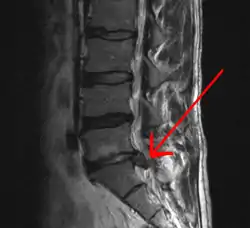

In most episodes, a specific underlying cause is not identified or even looked for, with the pain believed to be due to mechanical problems such as muscle or joint strain.[1][4] If the pain does not go away with conservative treatment or if it is accompanied by "red flags" such as unexplained weight loss, fever, or significant problems with feeling or movement, further testing may be needed to look for a serious underlying problem.[5] In most cases, imaging tools such as X-ray computed tomography are not useful and carry their own risks.[9][10] Despite this, the use of imaging in low back pain has increased.[11] Some low back pain is caused by damaged intervertebral discs, and the straight leg raise test is useful to identify this cause.[5] In those with chronic pain, the pain processing system may malfunction, causing large amounts of pain in response to non-serious events.[12]

An intervertebral disc has a gelatinous core surrounded by a fibrous ring.[34] When in its normal, uninjured state, most of the disc is not served by either the circulatory or nervous systems – blood and nerves only run to the outside of the disc.[34] Specialized cells that can survive without direct blood supply are in the inside of the disc.[34] Over time, the discs lose flexibility and the ability to absorb physical forces.[26] This decreased ability to handle physical forces increases stresses on other parts of the spine, causing the ligaments of the spine to thicken and bony growths to develop on the vertebrae.[26] As a result, there is less space through which the spinal cord and nerve roots may pass.[26] When a disc degenerates as a result of injury or disease, the makeup of a disc changes: blood vessels and nerves may grow into its interior and/or herniated disc material can push directly on a nerve root.[34] Any of these changes may result in back pain.[34]

Imaging is indicated when there are red flags, ongoing neurological symptoms that do not resolve, or ongoing or worsening pain.[5] In particular, early use of imaging (either MRI or CT) is recommended for suspected cancer, infection, or cauda equina syndrome.[5] MRI is slightly better than CT for identifying disc disease; the two technologies are equally useful for diagnosing spinal stenosis.[5] Only a few physical diagnostic tests are helpful.[5] The straight leg raise test is almost always positive in those with disc herniation.[5] Lumbar provocative discography may be useful to identify a specific disc causing pain in those with chronic high levels of low back pain.[43] Similarly, therapeutic procedures such as nerve blocks can be used to determine a specific source of pain.[5] Some evidence supports the use of facet joint injections, transforminal epidural injections and sacroilliac injections as diagnostic tests.[5] Most other physical tests, such as evaluating for scoliosis, muscle weakness or wasting, and impaired reflexes, are of little use.[5]